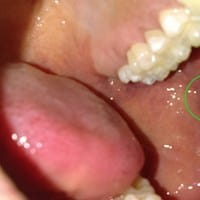

¿Absceso? Por dentro de mi mejilla

Yo creo que es litiasis salival lo que tiene el chico de la foto. A mi me salió algo parecido y buscando en internet, me di cuenta que eso era lo que yo tenía. La litiasis salival es cuando ocurre una obstrucción en una glándula salival o de su...